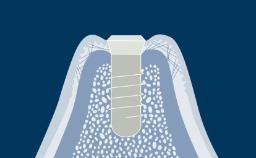

This Learning Module will outline the implant design features and characteristics that are aimed at facilitating integration with the hard and soft tissues, allowing them to serve as anchorage elements for prosthetic reconstructions whilst also withstanding occlusal loading forces.

- describe variations in the implant endosseous part

- describe variations in implant body materials and surface technology